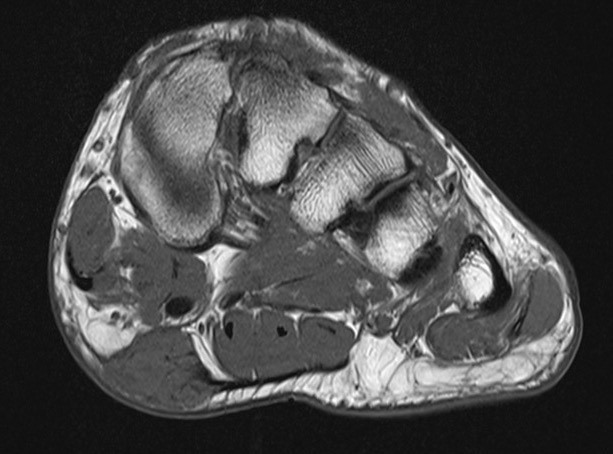

MRI

Focal oval shaped lesions within the plantar fascia

Usually affects medial and central bands of plantar fascia